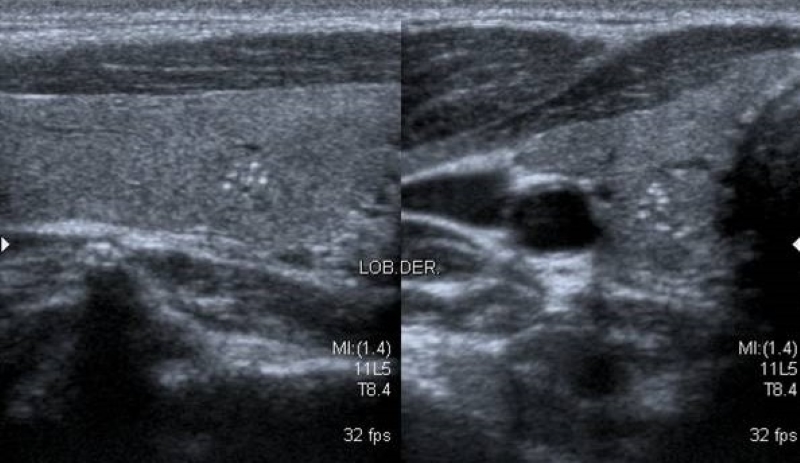

Calcificaciones

Focos ecogénicos que pueden clasificarse según su tamaño en microcalcificaciones (Fig. 15) y macrocalcificaciones (Fig. 16). Las primeras miden menos de 1 mm y no presentan sombra acústica posterior, a diferencia de las macrocalcificaciones que son mayores de 1 mm con sombra acústica posterior.

Las microcalcificaciones presentan un alto riesgo de malignidad. De hecho, algunos autores las consideran por sí solas un predictor de malignidad20, y otros sostienen que la presencia de microcalcificaciones sumado al aumento de la vascularización central y una imagen ganglionar patológica son suficientes para indicar una punción aspiración con aguja fina23.

El artefacto en cola de cometa (Fig. 17) es producido por la reverberación en los quistes coloides, que pueden confundir con microcalcificaciones. A diferencia de estas últimas, el artefacto en cola de cometa se visualiza como una línea ecogénica brillante con un triángulo o líneas ecogénicas posteriores, y se suele asociar a benignidad2.